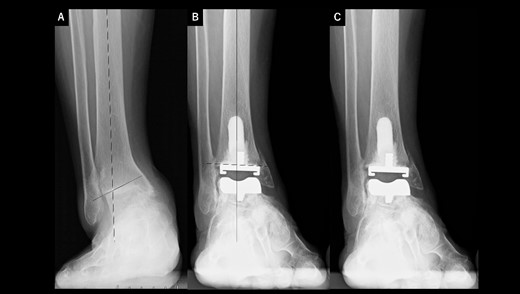

A 76-year-old woman with a 25-year history of RA [Clinical Disease Activity Index (DAS28-CRP score) 2.45: good control] had a JSSF ankle/hindfoot scale score of 42 points. She had been treated with 6 mg of methotrexate (MTX) per week. She complained of difficulty walking and ankle pain, resulting in an awkward gait. Talar tilt was 17° varus (Fig. 2A). She underwent TAA with medial malleolar osteotomy without internal fixation, and the tibial component was placed in the 2° varus position (Fig. 2B). Three years after TAA, she missed two or three steps while walking down the stairs. and developed anterior tibial pain. Radiography showed that varus migration of the tibial component had progressed (7° varus position; Fig. 2C), and she required revision TAA with internal fixation using a plate and allograft bone transplantation (Fig. 2D).

Radiographs of preoperative weight-bearing radiograph of the antero-posterior ankle joint in Case 2. (A) Preoperative. Talar tilt is 17° varus. Opening of the lateral gutter is seen. (B) One month after surgery. Medial malleolar osteotomy without internal fixation and the tibial component placed in the 2° varus position. Opening of the lateral gutter remains. (C) Three years after surgery. Varus migration of the tibial component has progressed after the patient missed the stairs (7° varus position of the component), and nonunion at the medial malleolar osteotomy has occurred. Opening of the lateral gutter has also remained. (D) Three months after revision surgery. Medial malleolar osteotomy site is fixed with a plate, and varus positioning of the tibial component still remains (3° varus). The lateral gutter is closed.